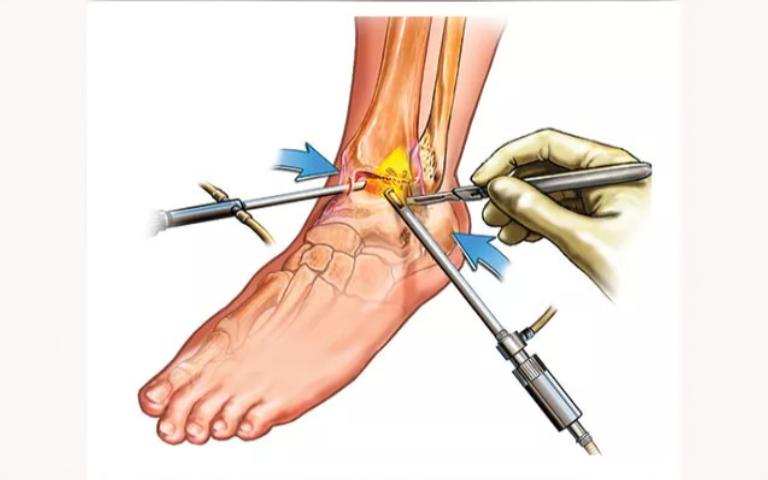

Mild tendon injuries often respond well to conservative care, including rest, physiotherapy, and anti-inflammatory treatment. More severe injuries, such as complete tendon tears, may require surgical repair or arthroscopic surgery in Islamabad to restore continuity and strength. Procedures are tailored to the patient’s age, activity level, and injury severity, performed by skilled orthopaedic doctors in Islamabad to optimise outcomes and reduce the risk of re-injury.